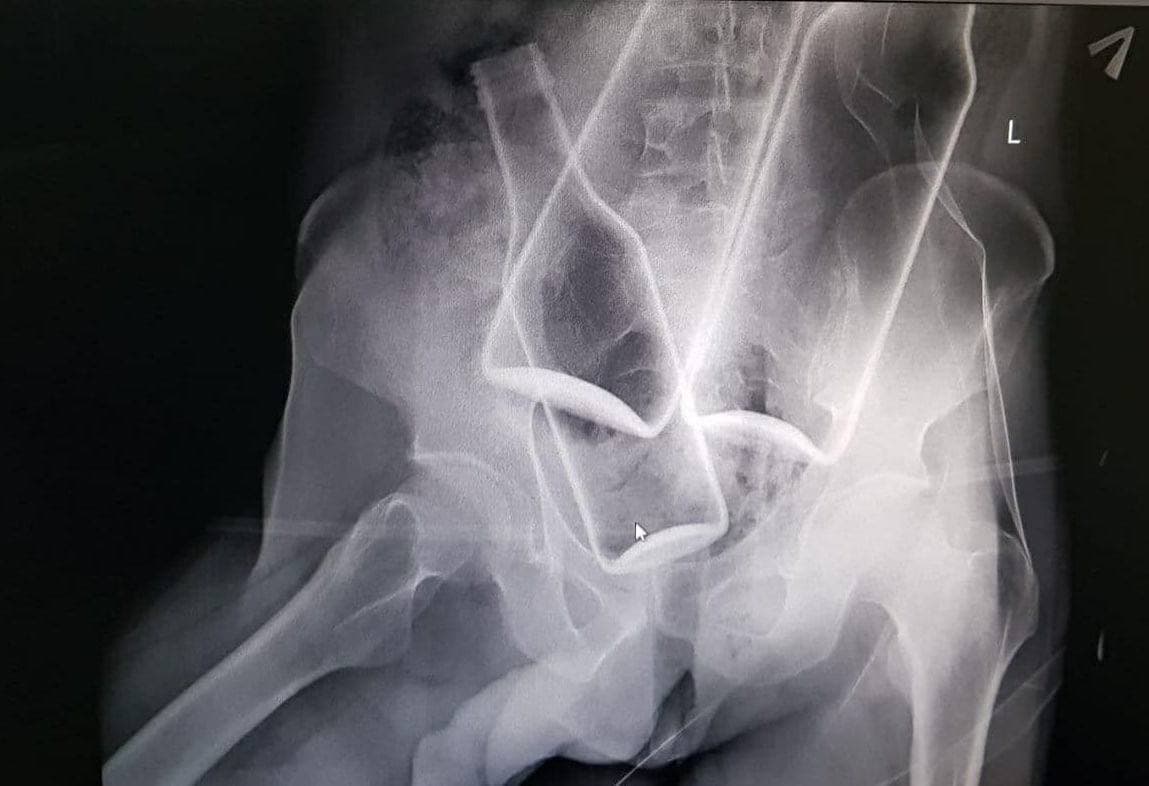

СК Москвы задержал мужчину, подозреваемого в убийстве человека. ЧП случилось в парке Сосенки в октябре 2020 года. Подозреваемым в убийстве оказался 21-летний дворник из района Котловка. Однажды он познакомился с мужчиной, своей будущей жертвой. А уже через несколько часов несчастный был госпитализирован в больницу, где позже и скончался. На рентгеновском снимке отчетливо видно, что дворник умудрился засунуть в свою жертву несколько пивных бутылок.